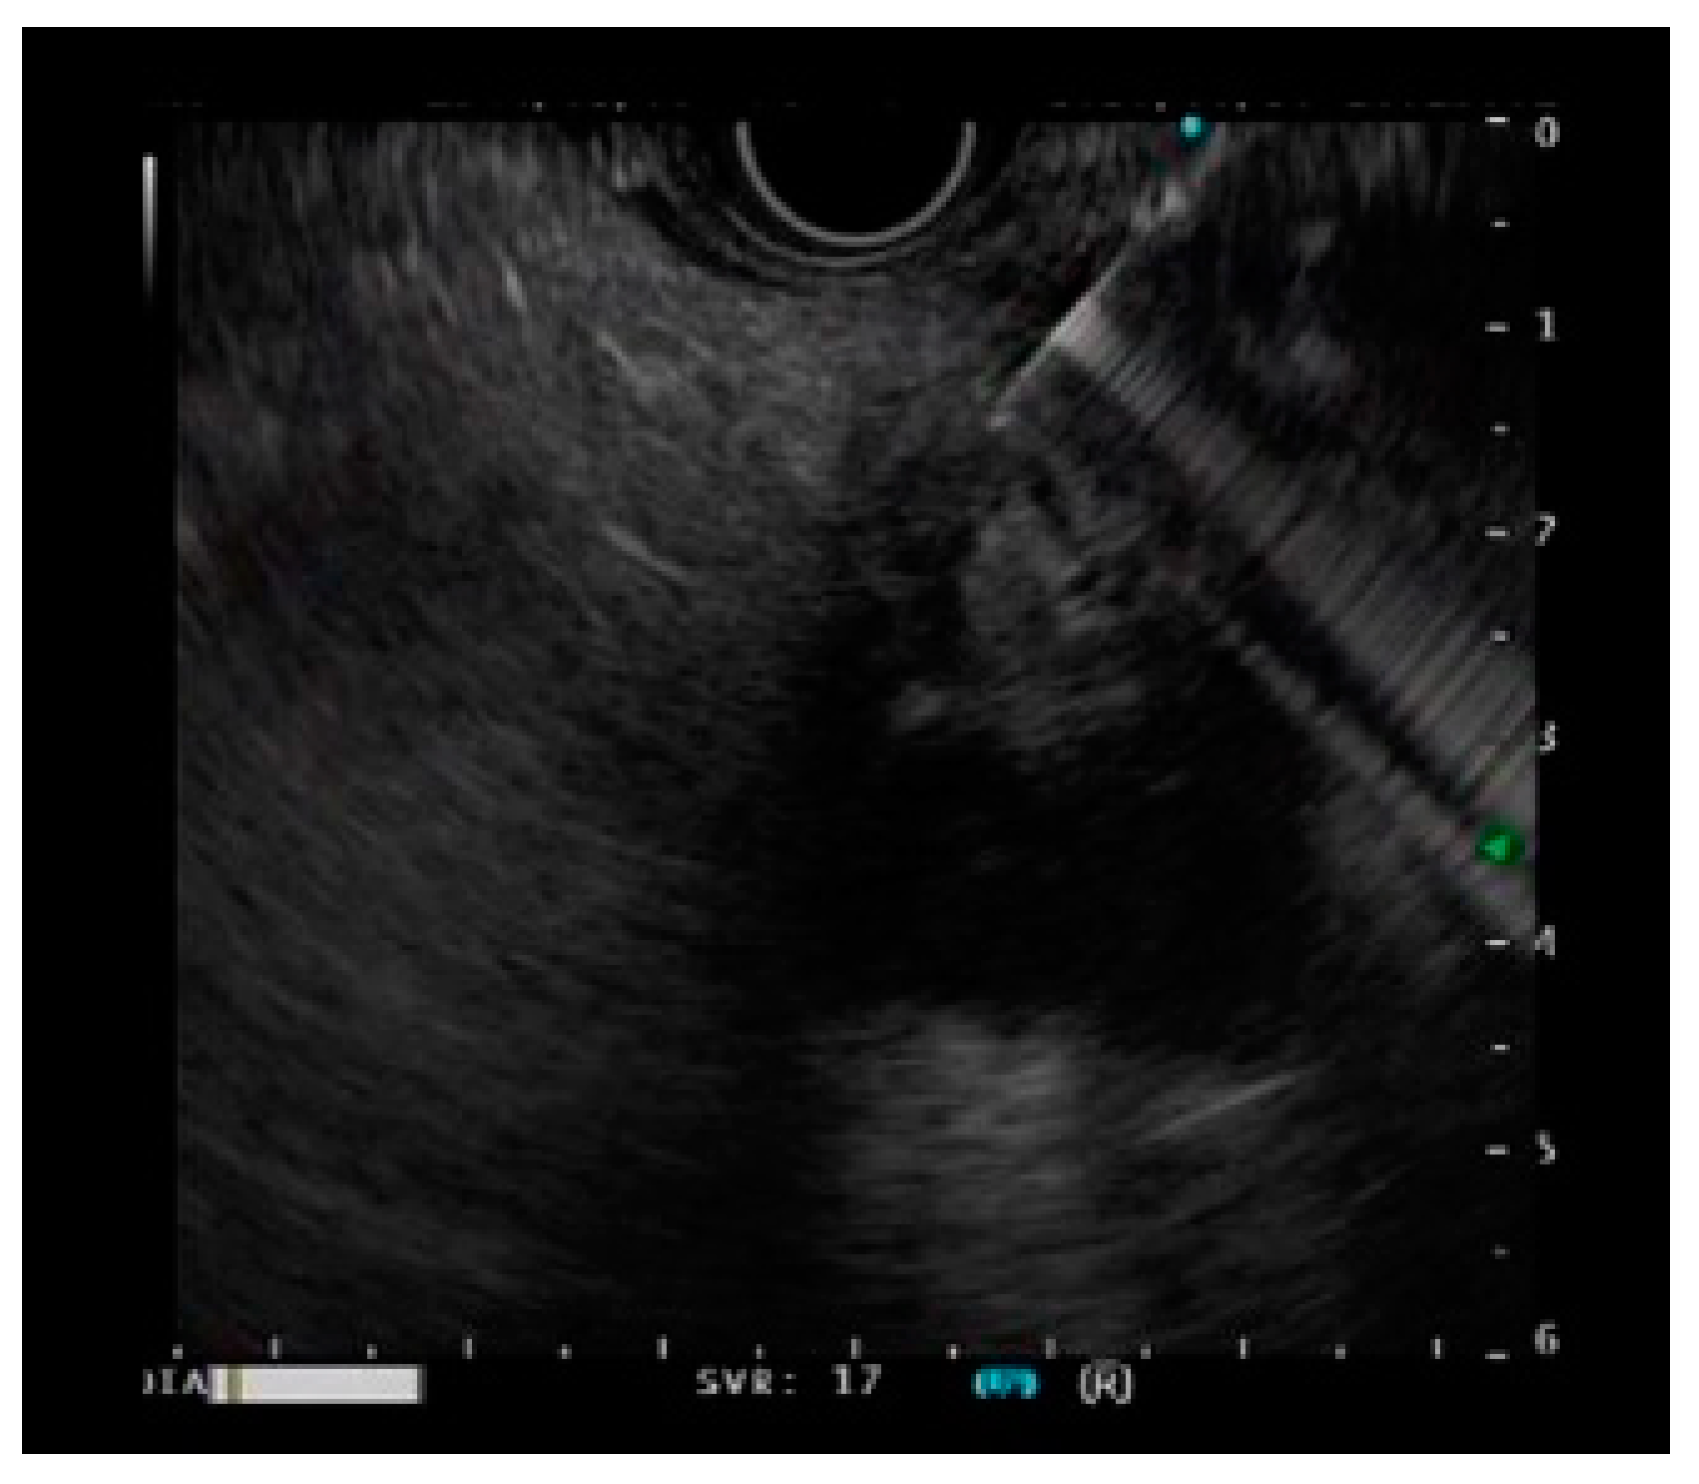

Effectiveness of EUS-Guided Fine-Needle Biopsy versus EUS-Guided Fine-Needle Aspiration: A Retrospective Analysis

2. Materials and Methods

3.3. Subgroup Analysis of SEL